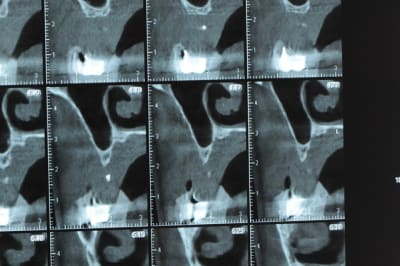

un cas pour PXAV.

ça c'est le domaine de pxav.

qu'en penses tu ?

j'ai besoin de 4 implants au maxillaire pour faire tenir son complet.

dans la zone postérieur, pas de problème, mais devant, c'est une autre histoire.

Non sans décorner, superbe cas de début pour expansion, bone splitting et tout et tout.

la corticale a l'air tiptop, par contre en cas d'expansion il faut eventuellemnt augmenter le nombre d'implant à 6 pour compenser eventuellement le manque d'epaisseur 'avis personnel)

Je suis sceptique sur la gestion de ce cas par bone splitting puisqu'il met parait très difficile d'obtenir un volume osseux peri-implantaire crestal suffisant et satisfaisant.

+1 Olive, ce serait à mon avis plus prédictible avec des greffes. Je doute qu'on puisse obtenir suffisamment d'os en vestibulaire et en palatin des implants en splittant une crête aussi fine.

De ce que j’ai vu du cas de D57 c’est me semble t il un magnifique cas d’expansion, ce qui ne veut pas dire rien d’autre

Ce n'est pas vraiment un consensus mais plutot du bon sens. Si tu as une crête en profil de lame de couteau cela signifie que tu as une fusion des corticales vestibulaire et palatine et donc absence de spongieux, ce qui comme tu le sais n'est pas indiqué en implanto (cj os de marbre par exemple)

Il me semble que Palti ou encore Szmukler-Moncler recommandent un minimum de 2-3mm. Si c'est plus fin, greffe d'apposition et GBR.

Dans ton cas il te faudrait abaisser la crête de 3 bons mm pour arriver à cette épaisseur.

Une petite étude de ton cas D57

Sous réserves bien sur de voir l’animal en vrai

Les zones exploitables radiologiquement parlant:

Coupes implant

2,3 40100

4,96 35130 avec sinus lift mais difficile

5,25 35150

6,02 35130

6,78 35115 après réduction de hauteur de crête

7,26 35115 après réduction de hauteur de crête

8,51 35150

10,43 40115 ou 50115

11,10 40115

Ce qui nous fait 9 implants possible évidement avec un comblement de sinus on augmenterait encore les zones implantable mais ce n’est pas le but recherché, avec 8 (4+4) il doit être possible de faire une belle barre support de complet